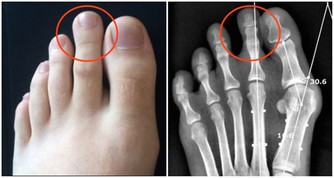

醫師建議乾癬患者務必注意關節症狀,像是早上起床,

關節紅腫脹痛特別明顯的人最好趕緊就醫,以免惡化至關節變形,造成不可挽回的悲劇。

2. 好發頭皮與肘膝:乾癬最常發生在頭皮、手肘、膝蓋等部位,

因為頻繁摩擦,導致皮膚會紅、變厚,而且有屑屑。